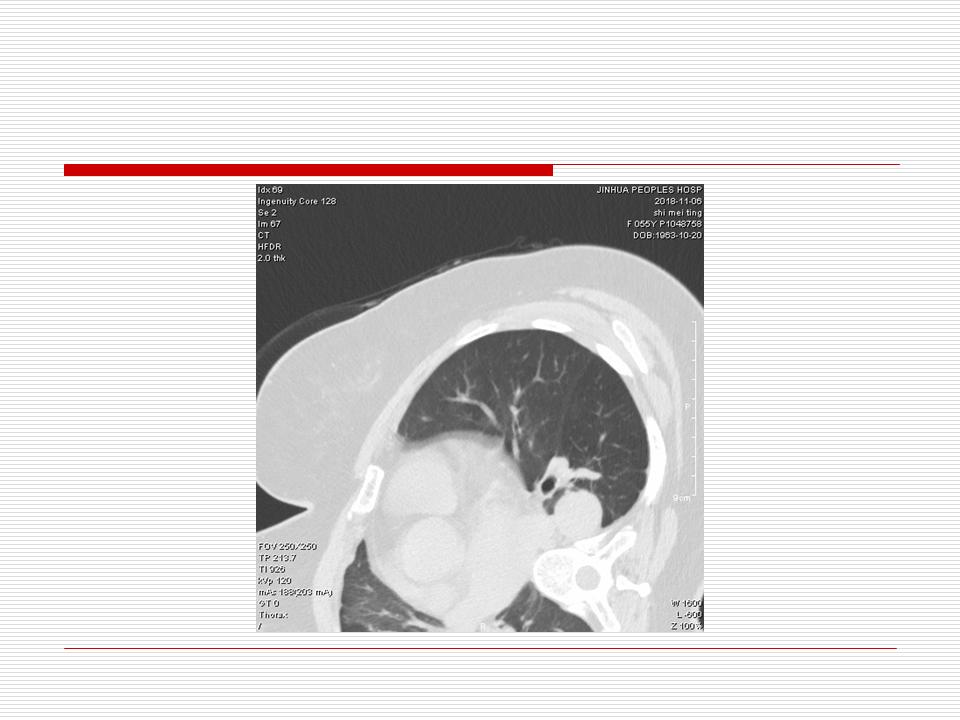

肺部阴影永恒且最重需要鉴别的是:到底是炎症还是肿瘤?但临床的病例中的影像表现难以界定或有些肿瘤特征,同时又有些炎症特点是非常常见的情况。作为临床医生我们怎么去总结分析,并找到之所以是炎症或之所以是肿瘤的细微差别或特点非常重要,也非常有用。2019.12.7浙江省2019年胸心外科学学术年会在宁波召开时,我的临床病例分析与经验总结<那些像肺癌的炎症与像炎症的肺癌>获得在大会交流的机会,以下为该PPT的内容,与你分享,希望对同道有益,有借鉴与启迪。若有探讨与进一不完善的建议,欢迎文末留言讨论: